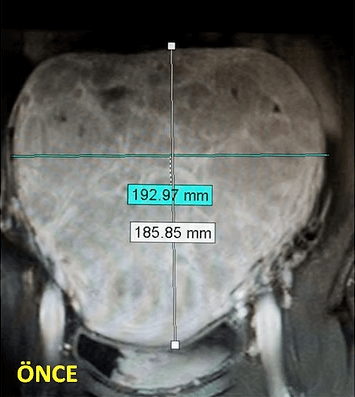

41 yaşında, kabızlık, gaz ve sık idrara çıkma şikayetleri var. Emar’da karını dolduran dev miyom (*) mevcut. Miyomektomi önerilmiş, ancak operasyonda rahimin alınabileceği söylenmiş. Embolizasyondan sonra dev miyomun ve bir başka küçük miyomun öldüğü ve küçüldüğü izleniyor. 7 ay sonra hasta şikayeti kalmamıştır.